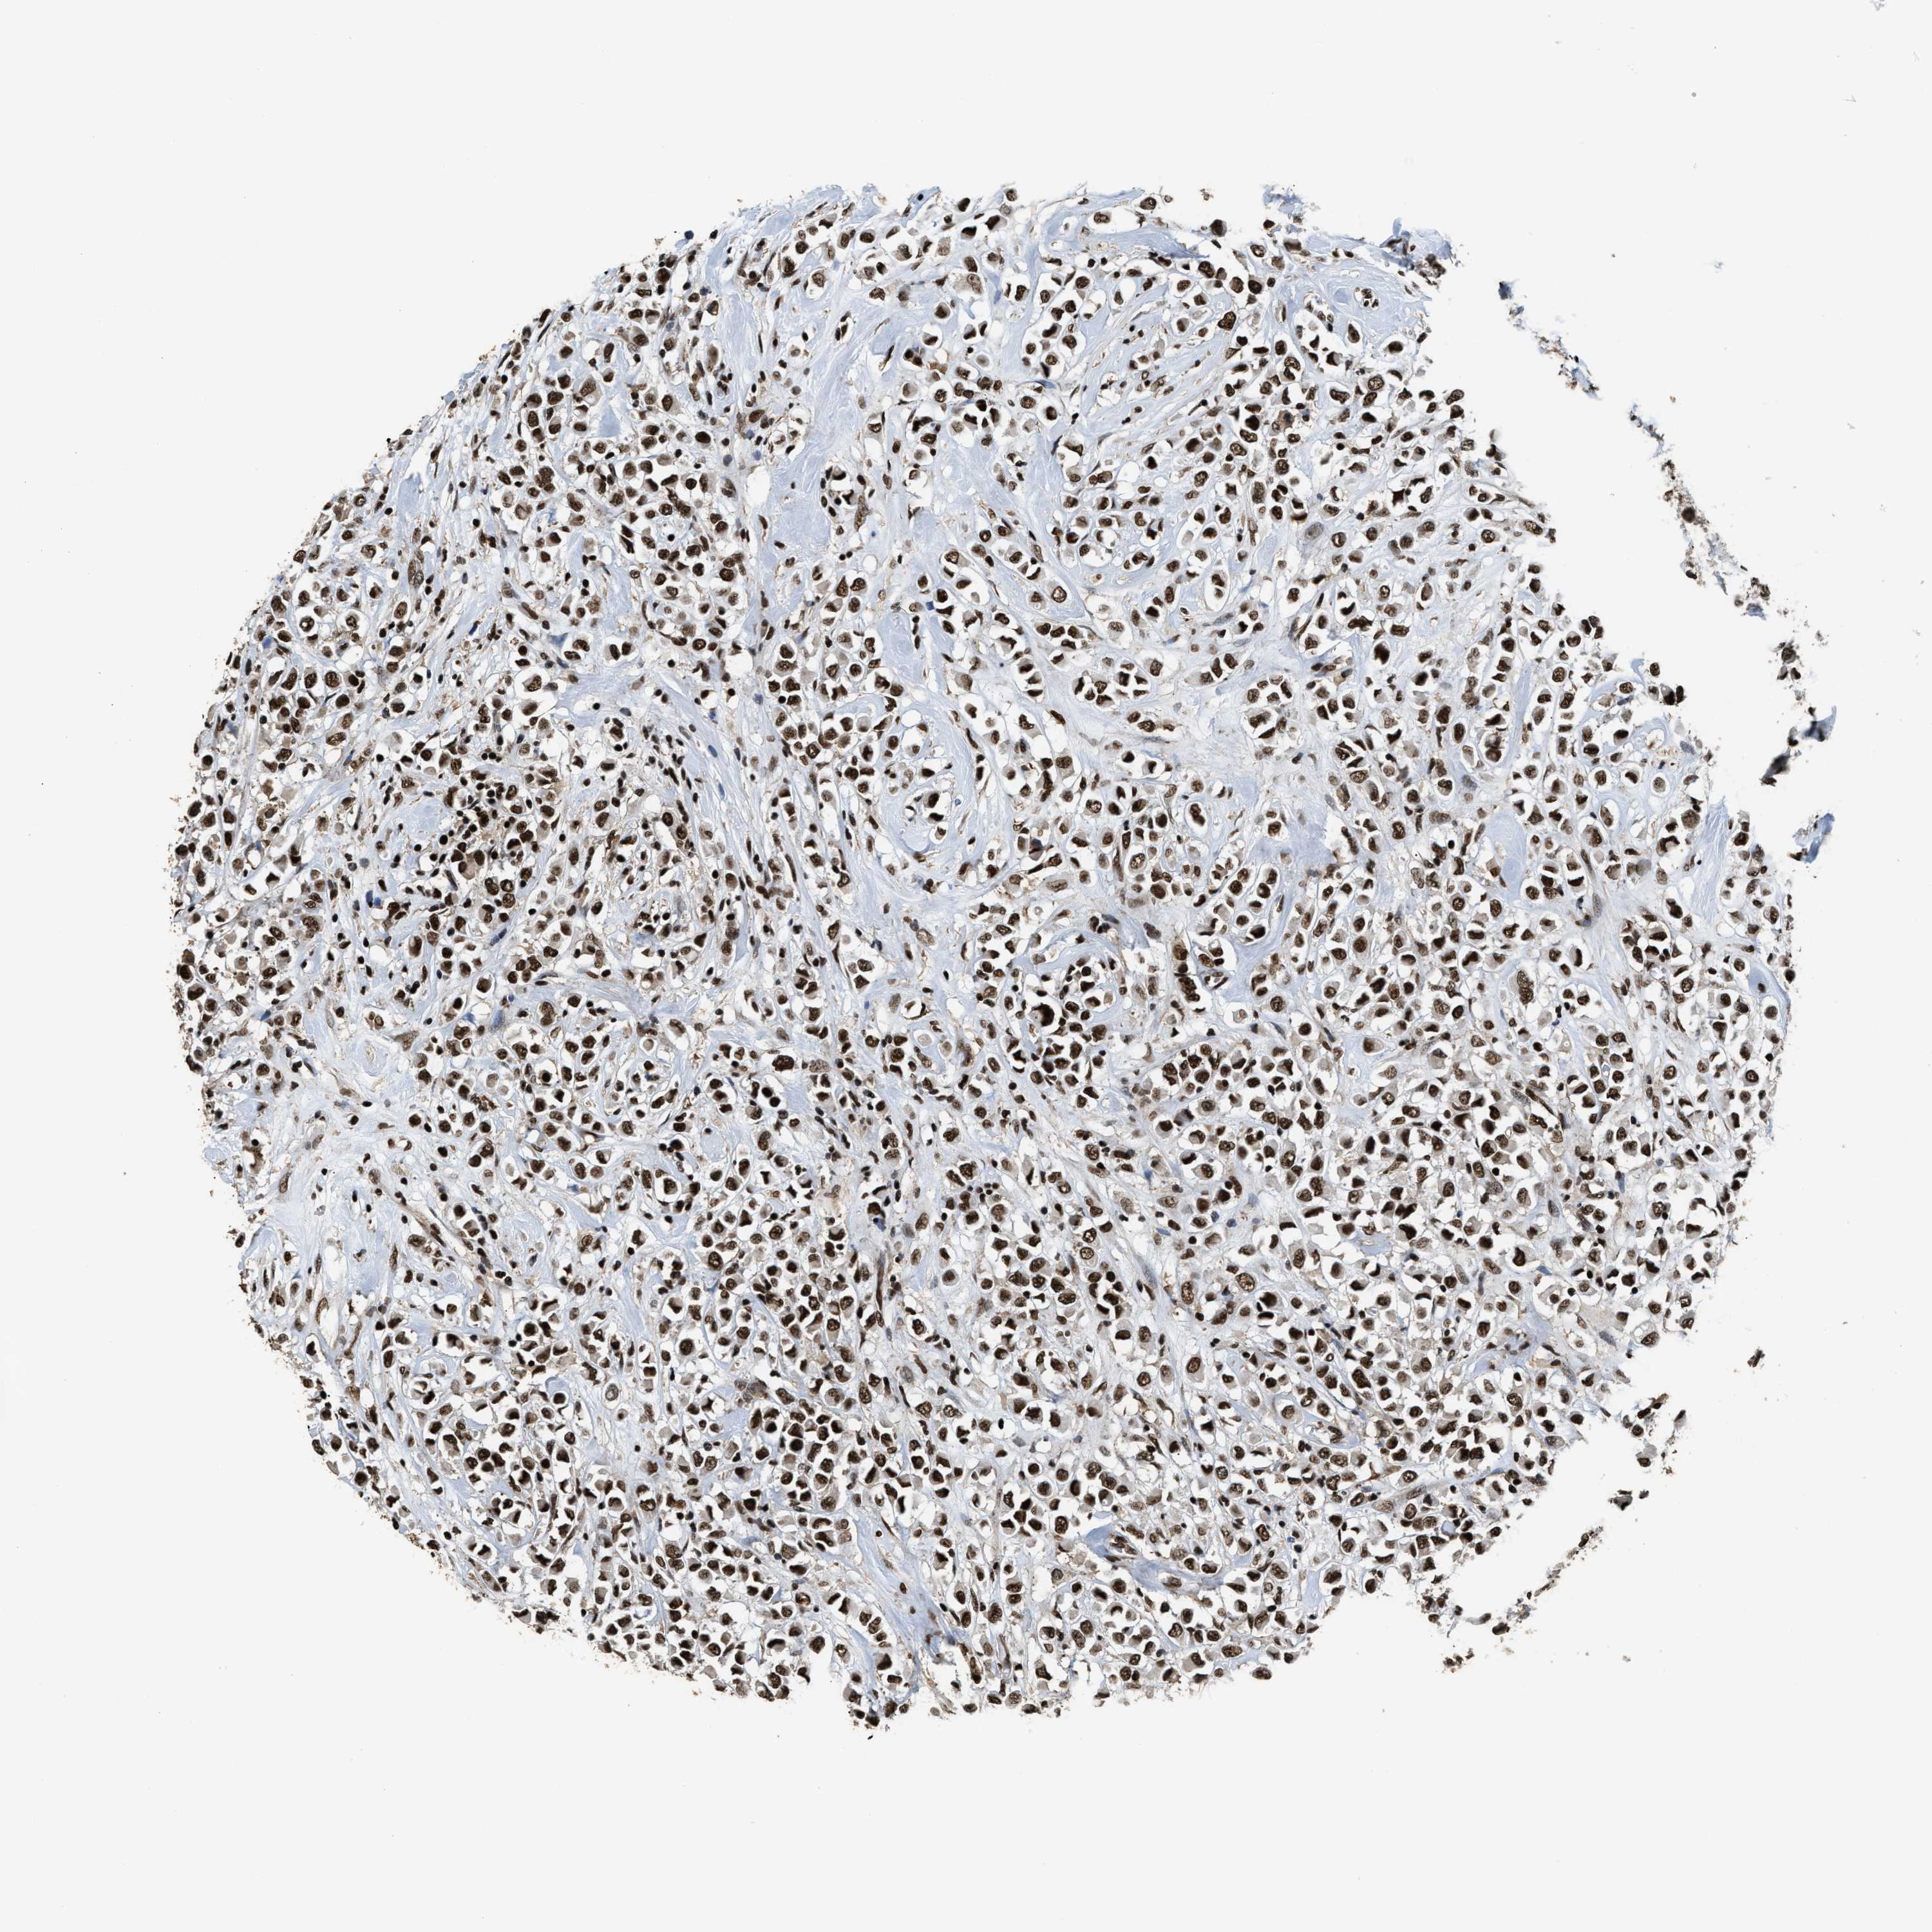

RAD21

CANCER BREAST CANCER Show tissue menu

BRCA TCGA BRCA VALIDATION PROTEIN EXPRESSION

ANTIBODIES

AND

VALIDATION